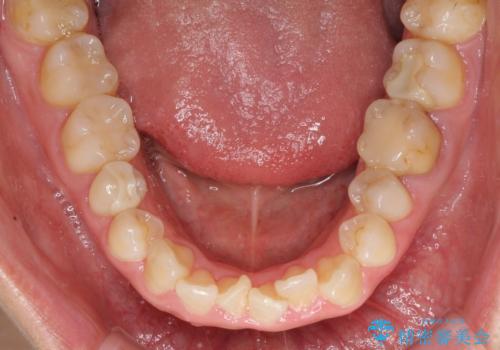

- 前歯の捻れを気にして来院された患者様です。

上顎前歯が捻れて前方に飛び出しており、下顎前歯もそれに沿うようにデコボコとなっていました。

IPR(歯と歯の間を削る処置)によりスペースを獲得して上下前歯のデコボコを改善し、インビザラインにて矯正治療を行うこととしました。